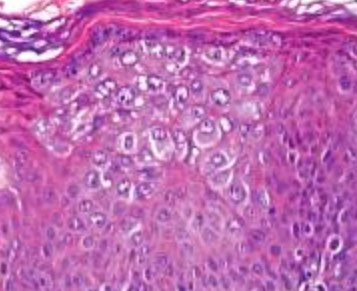

Histo: suprabasilar / intraepidermal blister and acantholysis

- "tombstones" - basal keratinocytes that remain attached to BM

IF: IgG and C3 deposition bwt cells in epidermis in fishnet or "chicken-wire" pattern

A) Pemphigus vulgaris, B) Pemphigus follicularis with suprabasal epidermal cleavage